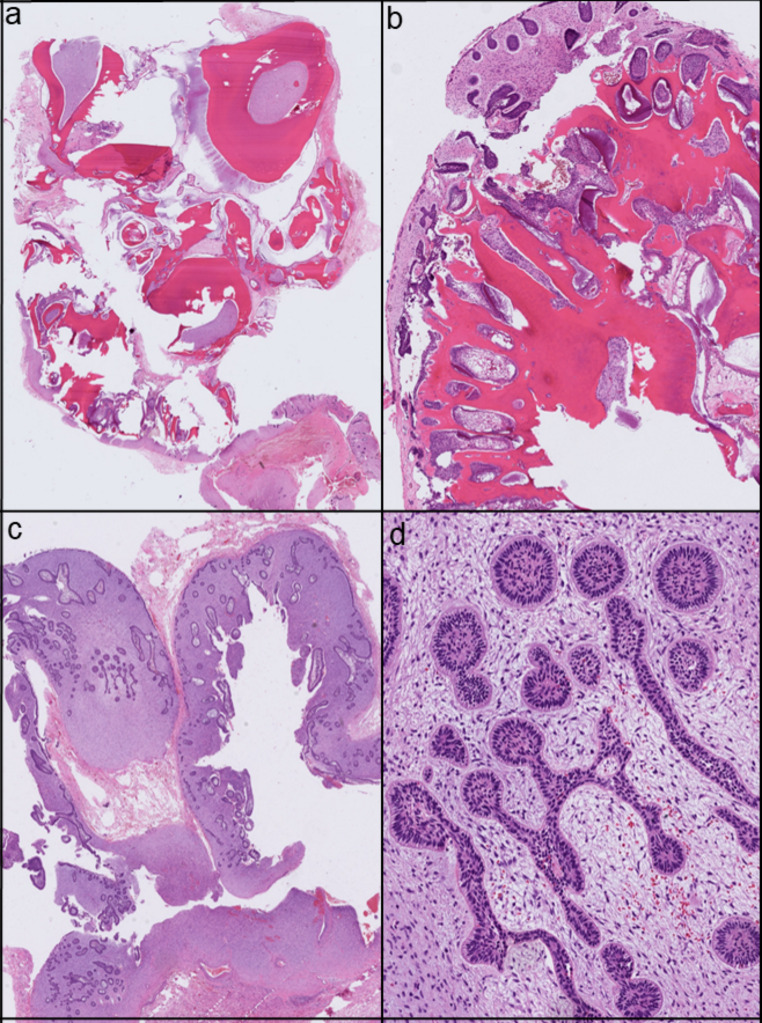

Methods: We present a case of an 8-year-old child with a slowly progressive swelling in the lower left mandible. Next-generation sequencing (TSO500 panel) was performed.

Results: Panoramic radiography revealed an odontogenic tumor; therefore, a transoral enucleation was performed. Pathological microscopic examination confirmed the diagnosis of AFO, and next-generation sequencing detected an FGFR1 mutation.